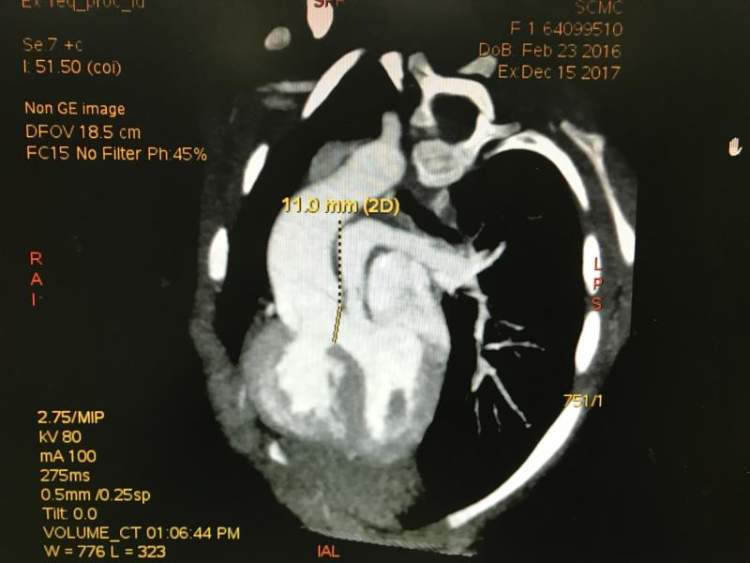

来自江西的患儿琪琪(化名)的心脏只有鸡蛋般大小,却同时存在着5处严重畸形,严重的缺氧,生长发育迟缓,22月的她似乎已经走到了生命的尽头。

琪琪的小心脏时同时存在着5处畸形。情况紧急,如不手术恐随时有生命危险。

郑景浩主任表示,双反心是一种非常罕见且复杂的先天性心脏病,发生率约为 0.5%。

除了医学上称之为矫正型大动脉转位的“双反心脏”外,还是IDD型(右位心),伴有两个心房的反位,以及左右肺动脉不对称狭窄。同时,其下腔静脉位于心房底部的中间,所有的这些加起来都极大地增加了手术的难度和风险。